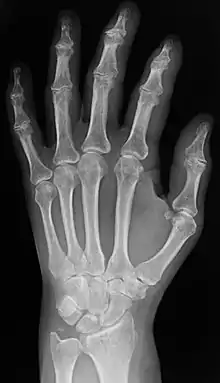

Plain x-ray of the wrist and hand

Radiography

Two forms of radiographic images are in use in medical imaging. Projection radiography and fluoroscopy, with the latter being useful for catheter guidance. These 2D techniques are still in wide use despite the advance of 3D tomography due to the low cost, high resolution, and depending on the application, lower radiation dosages with 2D technique. This imaging modality uses a wide beam of x rays for image acquisition and is the first imaging technique available in modern medicine.

• Projectional radiographs, more commonly known as x-rays, are often used to determine the type and extent of a fracture as well as for detecting pathological changes in the lungs. With the use of radio-opaque contrast media, such as barium, they can also be used to visualize the structure of the stomach and intestines – this can help diagnose ulcers or certain types of colon cancer.